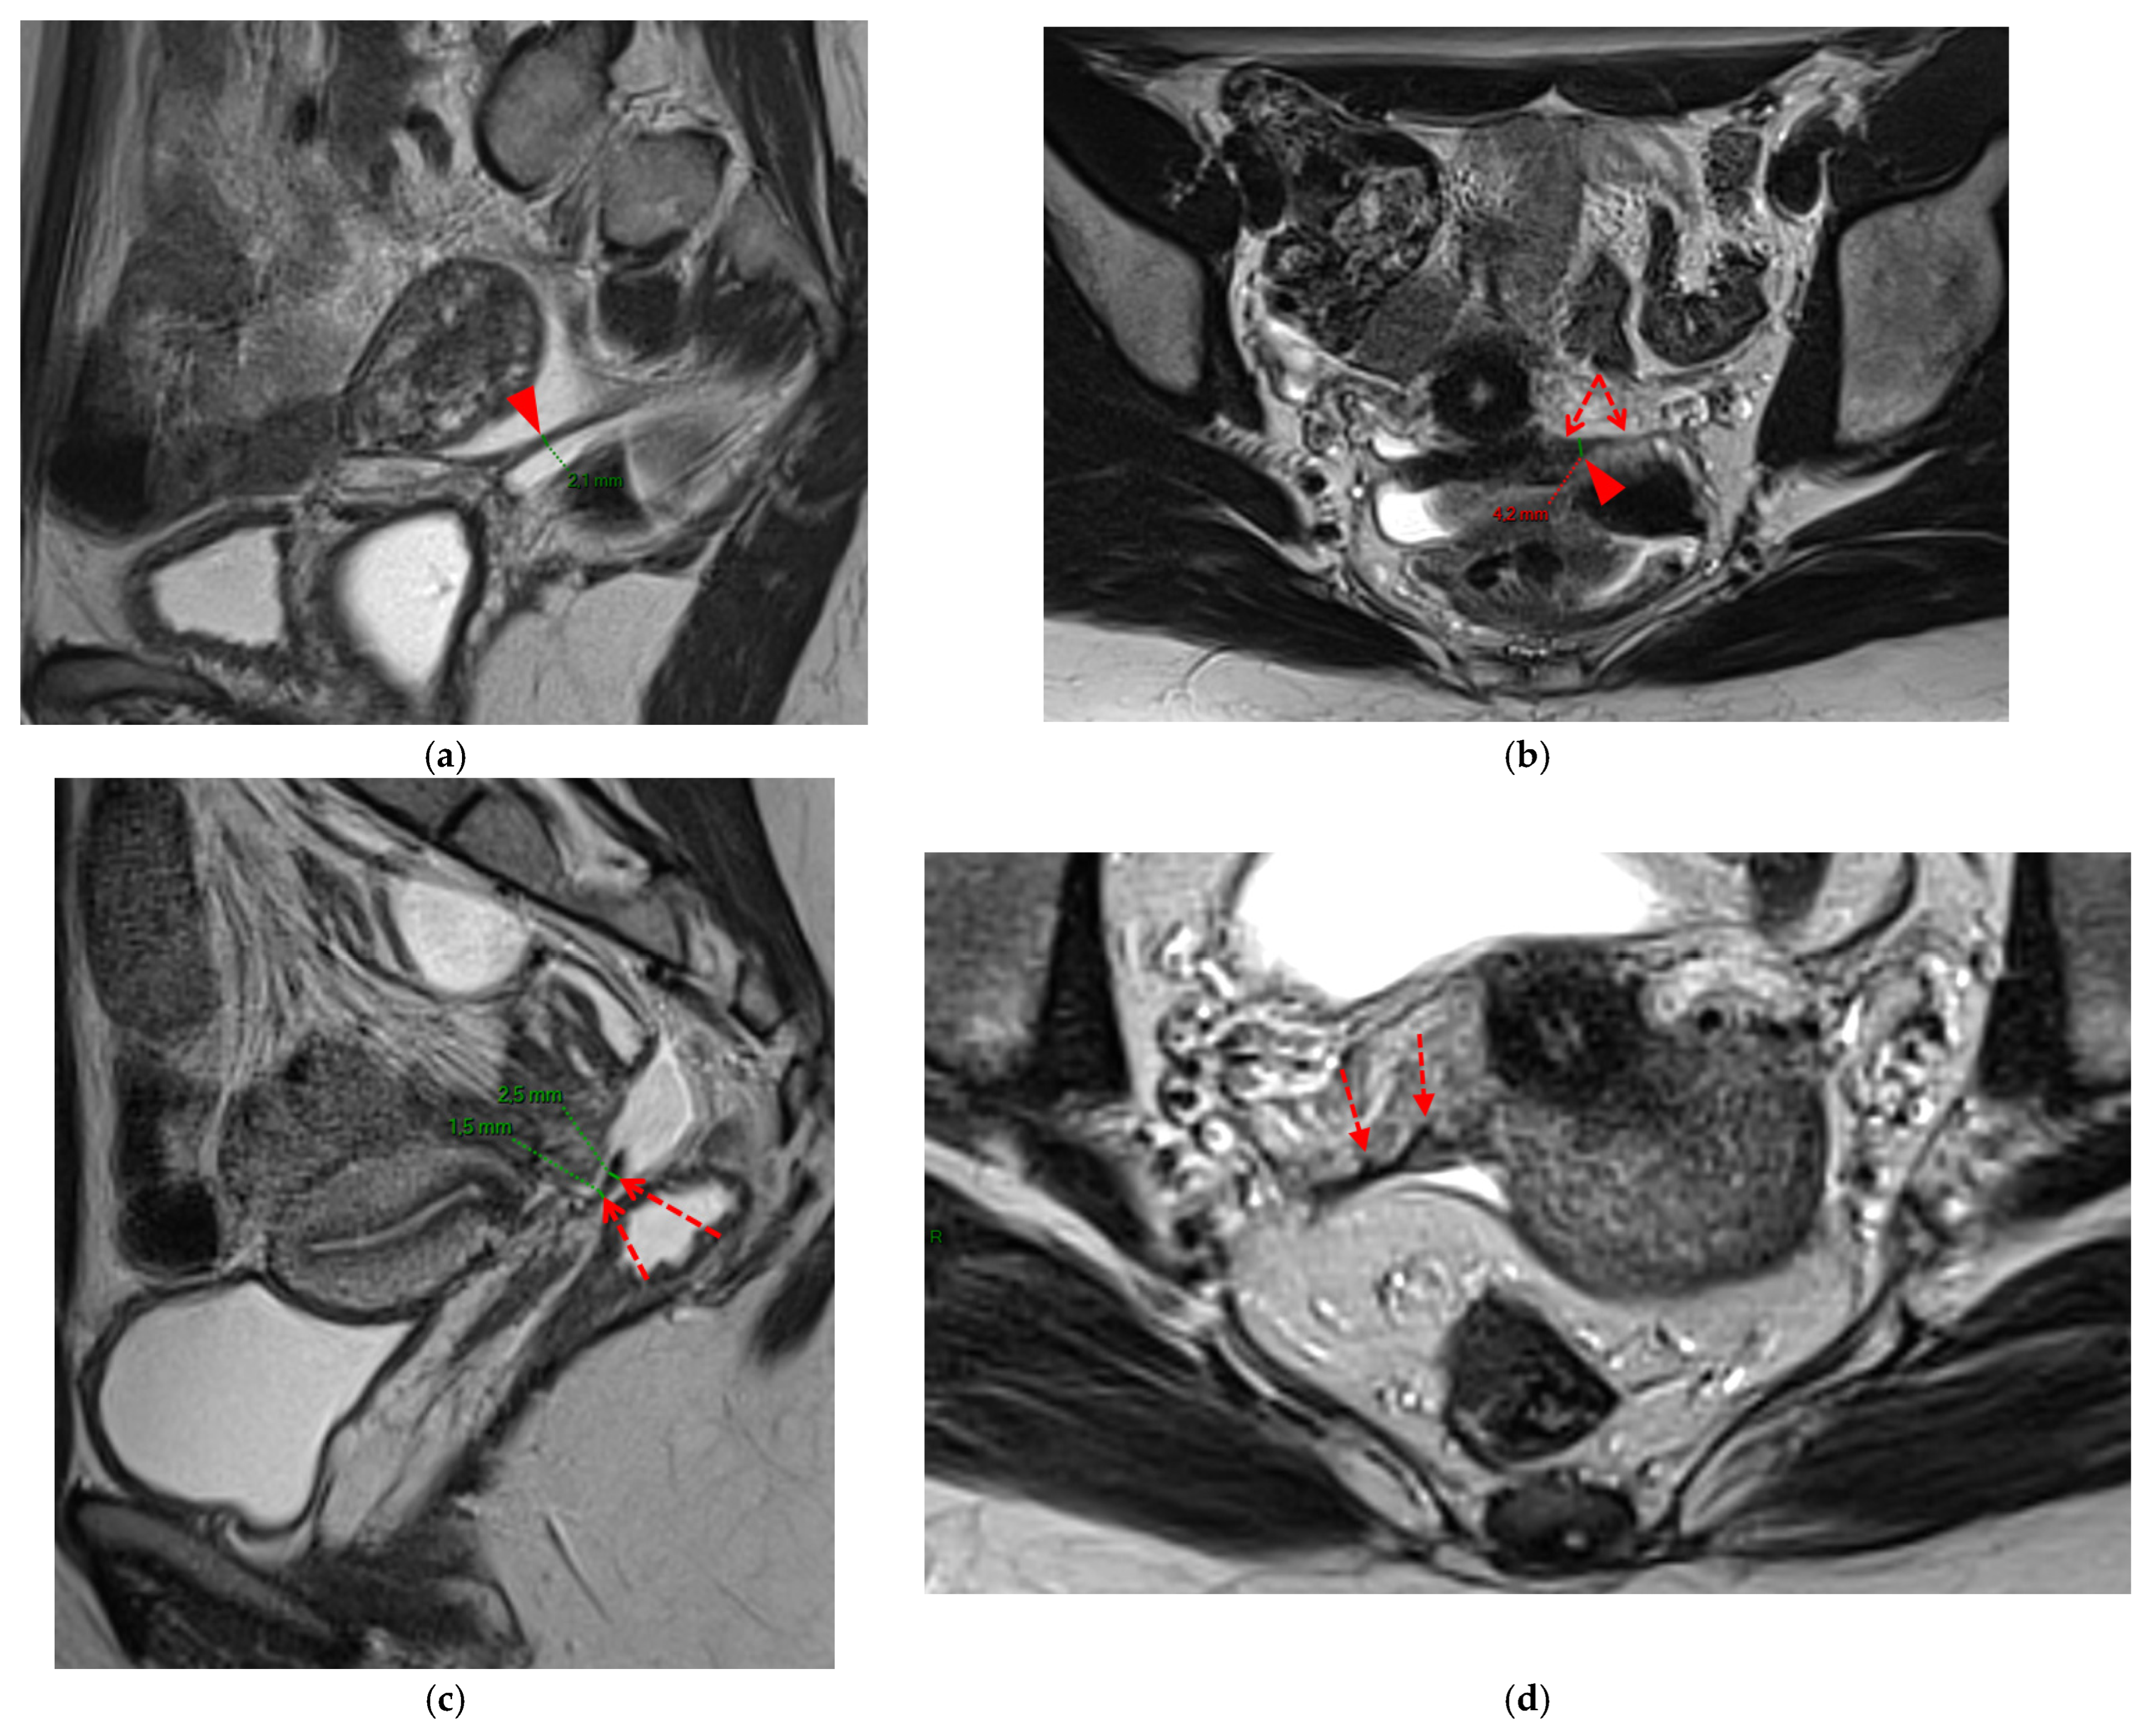

Figure 4. Pelvic MRI scans of seven patients with HTD type 3B USLs. (a) Sagittal T2WI: a thickened (2.1 mm) and stiffened right USL (arrowhead) with “bowstringing”. (b) Axial T2WI: a caliber disparity (dashed arrows) with focal thickening (4.2 mm) of the left proximal USL (arrowhead). (c) Sagittal T2WI: a caliber disparity (dashed arrows) with focal thickening (2.5 mm) of the right distal USL. (d) Axial T2WI: a right USL with a notched and irregular surface (dashed arrows). (e) Axial T2WI: thickened and stiffened left (3 mm) and right (2.5 mm) USLs with “bowstringing” of both USLs (arrowheads). (f) Sagittal T2WI: a thickened (2.6 mm) right USL with a stiffened appearance characterized by a steep vertical orientation (arrowhead). (g) Sagittal T2WI: the right USL appears thin (1.9 mm) but stiffened (arrowhead), exhibiting “bowstringing”. These findings led to its reclassification from type 2 to type 3B.

A type 3B USL (Figure 4), in addition to being thickened, has a notched surface with slightly irregular margins, or a caliber disparity with focal thickening, or appears “stiffened”, which means it loses its curvilinearity to exhibit a steep vertical orientation in the sagittal plane or a “bowstringing” of the USL in the sagittal or axial planes. Occasionally, a USL might appear thin but “stiffened”, which would upgrade it from a type 2 to a type 3B.